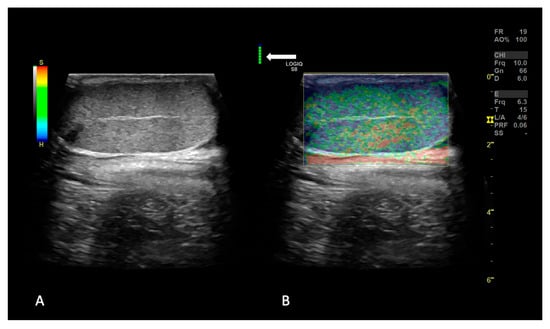

2.1.2. SE and 2D SWE Examination

3.3. 2D Shear Wave Elastography